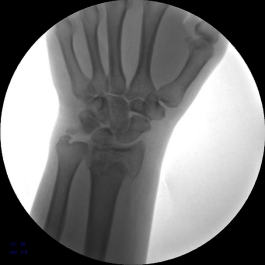

患者男,48岁,主诉外伤致右腕部疼痛,活动受限7天。于南阳市骨科医院行手法整复后患者对治疗效果不满意,遂手术治疗。

1.初步手法复位